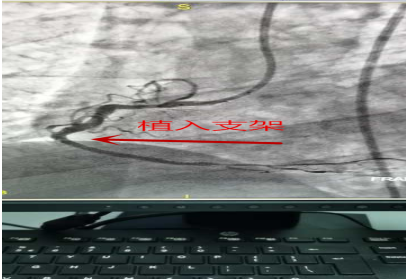

术后效果: